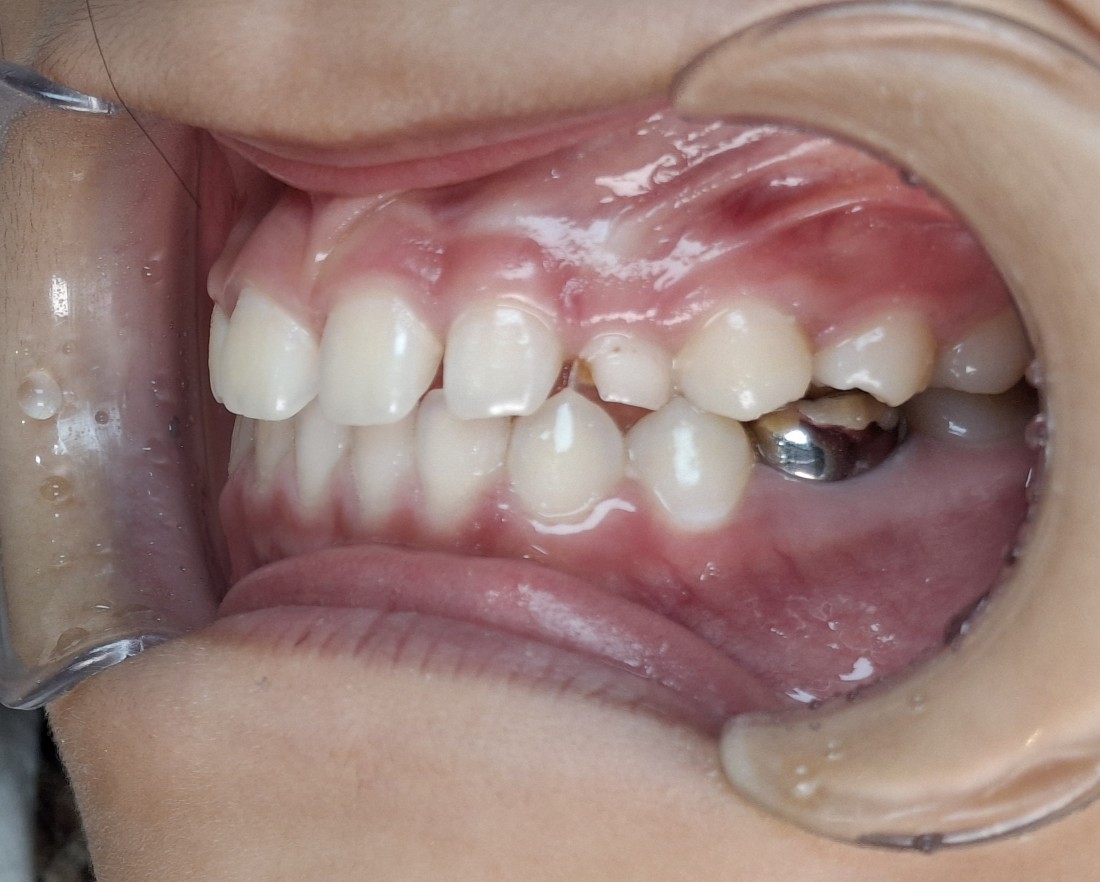

소아부정교합 중에서

반대교합의 경우에는

정상교합에 비하여

아랫니, 아래턱이 많이 튀어나와 있어

부모님들께서도 조기에 발견하실 수 있는데요.

프리올소를 사용하기 최적의 나이는

만5세 ~ 12세 사이의

혼합치열기 (유치에서 영구치로 교환되는 시기)

이기 때문에,

이 골든타임을 잘 지키는 것이

무엇보다도 중요합니다.